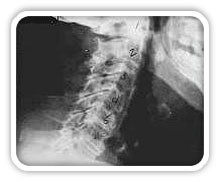

Phase Three Subluxation Degeneration

Phase Three Subluxation Degeneration is caused by subluxations that have been continuing on for between 40 and 65 years. This phase has all of the attributes of the previous phases, only worse. The curvatures are abnormal, the disc spaces are vastly decreased and changed. Calcium changes on the spine are abundant in this phase. Normally, people in phase three have a restricted range of motion and probably exhibit symptoms of some kind. In phase three the vertebrae show obvious changes and mutations in shape. Projections made of calcium, sometimes referred to as "spurs or lipping", can be readily seen on x-ray. Chiropractic reconstructive care for patients in phase three ranges from 2.5 years to 3.5 years. This does not mean that at the end of this time that any or all of the calcium changes will be gone. In many instances the body adapts to the presence of the calcium and positive changes can only be measured from a functional standpoint. As before, if Phase Three Subluxation Degeneration is left unchecked it slowly advances onward into the next phase.

Phase Four Subluxation Degeneration

Phase four subluxation degeneration is seen with subluxations that have been raging on uncorrected or altered for over sixty five years. Phase four is a grave condition that will negatively affect the patients longevity and quality of life. The massive amount of neurological damage caused by years of subluxation that have lead to phase four are probably taking a serious toll on this person's health status. X-rays in phase four show serious severe structural changes. Vertebrae exhibit massive calcium changes, disc spaces appear blurred, and the bones themselves appear fused. In this scenario the patient will have a severe restriction of range of motion in addition to probably a number of other health issues. Reconstruction may not be possible in phase four, but care can be directed to some reduction in subluxation with the goal of improvement in the quality of life remaining. Patients in Phase Four Subluxation Degeneration have a serious situation both structurally and neurologically, but they are certainly not beyond hope. Many patients in phase four report significant improvements in symptoms, conditions, mobility and quality of life.